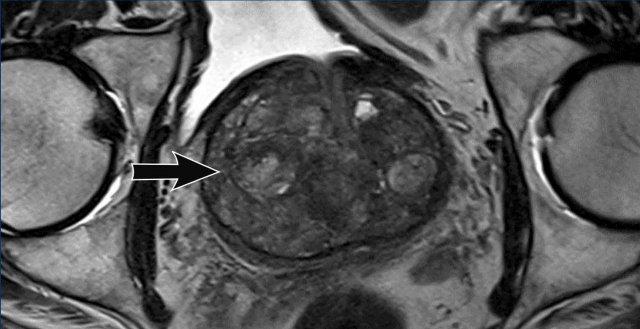

Ở đây chúng ta thấy sự khác biệt giữa viêm tuyến tiền liệt (hình bên trái) và ung thư tuyến tiền liệt (hình bên phải).

Bên trái

Các hình bên trái cho thấy một vùng hình nêm giảm tín hiệu nhẹ trên chuỗi xung T2W và ADC mà không có tín hiệu cao tương ứng trên DWI, nằm ở phía lưng trong vùng ngoại vi bên phải của phần giữa tuyến tiền liệt (mũi tên vàng).

Được diễn giải là viêm khu trú (phân loại PI-RADS 2).

Không thực hiện sinh thiết.

Bên phải

Các hình bên phải cho thấy ung thư tuyến tiền liệt có ý nghĩa lâm sàng với vùng giảm tín hiệu rõ rệt, bờ không rõ trên chuỗi xung T2W và ADC, và tăng tín hiệu khu trú trên DWI ở phía lưng trong vùng ngoại vi bên trái (phân loại PI-RADS 4).

Sinh thiết có hướng dẫn MRI cho thấy điểm Gleason 4+3.